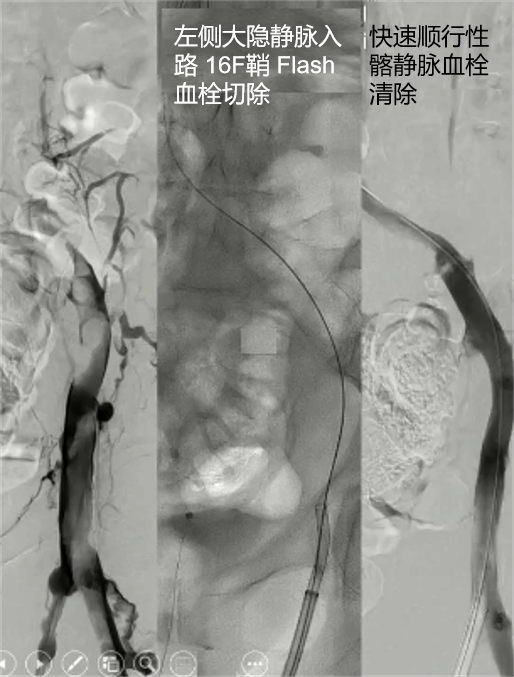

Lightning Flash导管兼容16-F鞘,采用MaxID技术,使其具有较大的内径,同时保持较低的轮廓,优化了其低轮廓尺寸,使其非常可追踪和无创,但同时也非常强大,能够导航通过复杂的解剖结构并移除大量的血栓负担。

通过腘窝途径可处理同侧深部开口病变 经对侧途径进行深部/腘窝处操作

三、Penumbra Indigo 如何用于静脉血栓治疗?手术过程(简要):微创入路:

医生通过患者颈部、腹股沟或膝盖后侧的静脉经皮穿刺进入静脉靶血管。

建立通路:

在影像设备的引导下,将导丝和导管鞘送至血栓部位。

抽吸血栓:

将Indigo抽吸导管穿过导管鞘,直达血栓内部。启动抽吸泵,产生负压,将血栓吸入导管并收集到专用的血栓收集瓶中。同时,医生会操作分离器来优化抽吸效果。

评估与完成:

通过造影确认血栓已被成功清除,血流恢复后,撤出器械,手术结束。